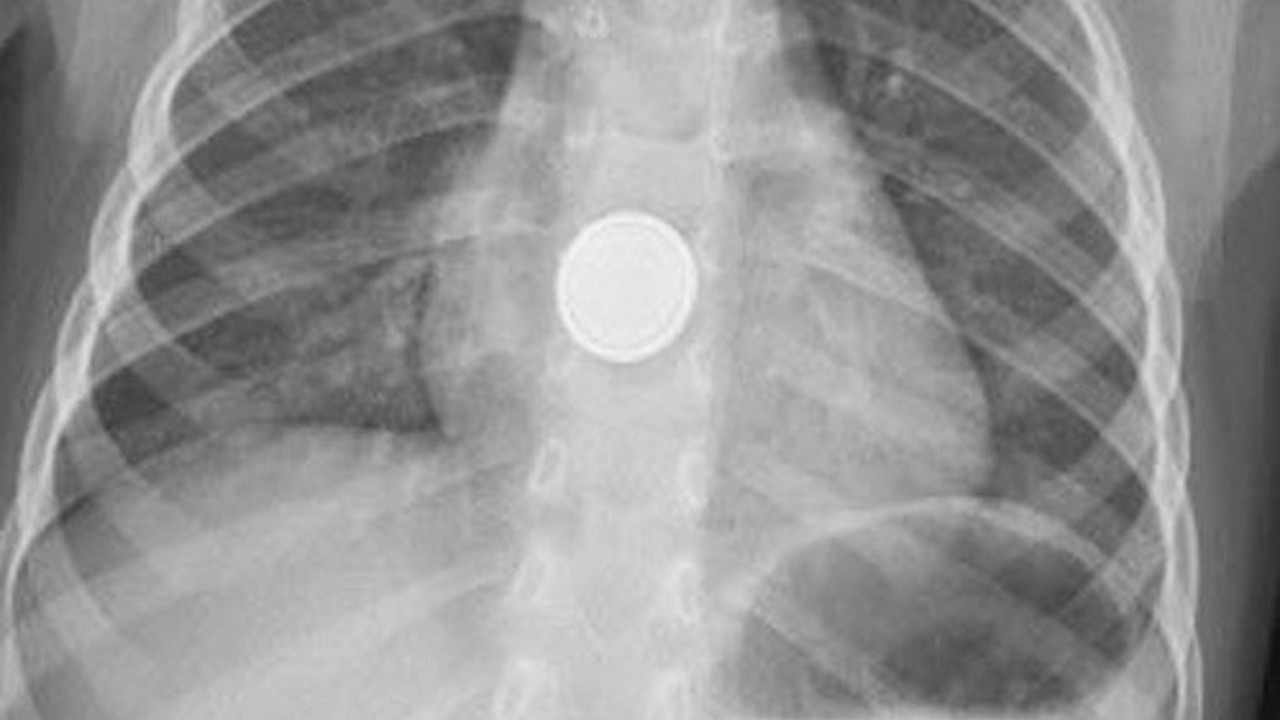

Tarsuslu İbrahim ve Sibel Işık çiftinin tek çocukları Mehmet Efe Işık, evde oyun oynarken, baskülün 3.5 santimetre çapında ve 2 milimetre kalınlığındaki yuvarlak pilini yerinden çıkarıp yuttu. Küçük çocuk, ağzına aldığı pili yuttuktan kısa süre sonra yemek borusunda yanma hissetti. Annesinin yanına giden çocuk, 'Ben pil yuttum. Boğazım yanıyor' demesi üzerine ailesi tarafından hemen Medical Park Hastanesi Acil Servis'e götürüldü. Küçük çocuk, ağzına aldığı pili yuttuktan kısa süre sonra yemek borusunda yanma hissetti. Annesinin yanına giden çocuk, 'Ben pil yuttum. Boğazım yanıyor' demesi üzerine ailesi tarafından hemen Medical Park Hastanesi Acil Servis'e götürüldü. Acil Servis'te ilk müdahalesi yapılan ve filmi çekilen Mehmet Efe'yi ardından Gastroenteroloji Uzmanı Dr. Hüseyin Sancar Bozkurt'a yönlendirdi. Bozkurt ve ekibi, endoskopik yöntemle yaklaşık yarım saatlik bir çalışmayla pili çocuğun boğazından çıkardı. Pilin çevresindeki dokuyu yakarak hasar verdiği belirlendi. Minik Mehmet Efe, hastanede 4 gün tedavi gördükten sonra, yeme içme fonksiyonlarının yerine gelmesi üzerine taburcu edildi. Dr. Hüseyin Sancar Bozkurt, küçük çocuklarda pil yutma vakalarına zaman zaman rastlandığını, ancak bu olayda çocuğun yemek borusunun yandığını söyledi.